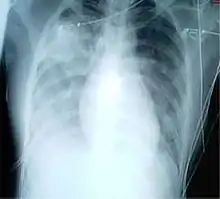

For a case to be considered probable, a chest X-ray must be indicative for atypical pneumonia or acute respiratory distress syndrome.

The WHO has added the category of "laboratory confirmed SARS" which means patients who would otherwise be considered "probable" and have tested positive for SARS based on one of the approved tests (ELISA, immunofluorescence or PCR) but whose chest X-ray findings do not show SARS-CoV infection (e.g. ground glass opacities, patchy consolidations unilateral).[11][12]

The appearance of SARS-CoV in chest X-rays is not always uniform but generally appears as an abnormality with patchy infiltrates.[13]